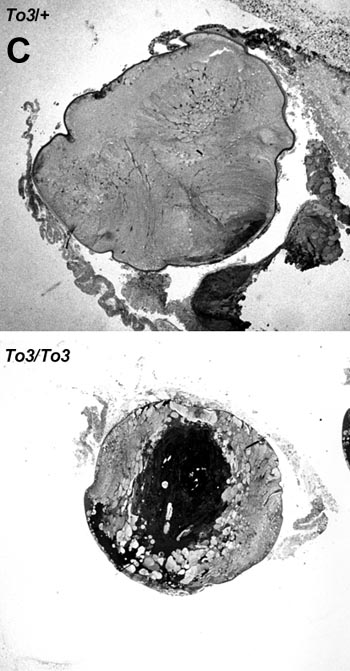

Figure 8. Histological analysis of transgenic mouse eyes

Panel A shows representative E15 eye sections. Sections of eyes from wild type (+/+), hemizygous transgenic (To3/+), and homozygous transgenic (To3/To3) siblings. Panel B shows representative E19 eye sections. Sections of eyes from wild type (+/+), hemizygous transgenic (To3/+), and homozygous transgenic (To3/To3) siblings. Panel C shows representative P18 eye sections. Sections of eyes are from hemizygous transgenic (To3/+), and homozygous transgenic (To3/To3) siblings.